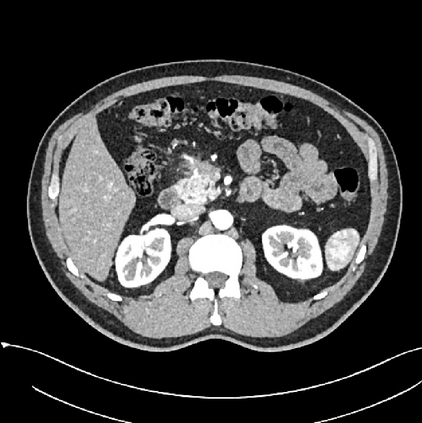

Early tumor detection save lives. Each year, more than 300 million computed tomography (CT) scans are performed worldwide, offering a vast opportunity for effective cancer screening. However, detecting small or early-stage tumors on these CT scans remains challenging, even for experts. Artificial intelligence (AI) models can assist by highlighting suspicious regions, but training such models typically requires extensive tumor masks--detailed, voxel-wise outlines of tumors manually drawn by radiologists. Drawing these masks is costly, requiring years of effort and millions of dollars. In contrast, nearly every CT scan in clinical practice is already accompanied by medical reports describing the tumor's size, number, appearance, and sometimes, pathology results--information that is rich, abundant, and often underutilized for AI training. We introduce R-Super, which trains AI to segment tumors that match their descriptions in medical reports. This approach scales AI training with large collections of readily available medical reports, substantially reducing the need for manually drawn tumor masks. When trained on 101,654 reports, AI models achieved performance comparable to those trained on 723 masks. Combining reports and masks further improved sensitivity by +13% and specificity by +8%, surpassing radiologists in detecting five of the seven tumor types. Notably, R-Super enabled segmentation of tumors in the spleen, gallbladder, prostate, bladder, uterus, and esophagus, for which no public masks or AI models previously existed. This study challenges the long-held belief that large-scale, labor-intensive tumor mask creation is indispensable, establishing a scalable and accessible path toward early detection across diverse tumor types. We plan to release our trained models, code, and dataset at https://github.com/MrGiovanni/R-Super